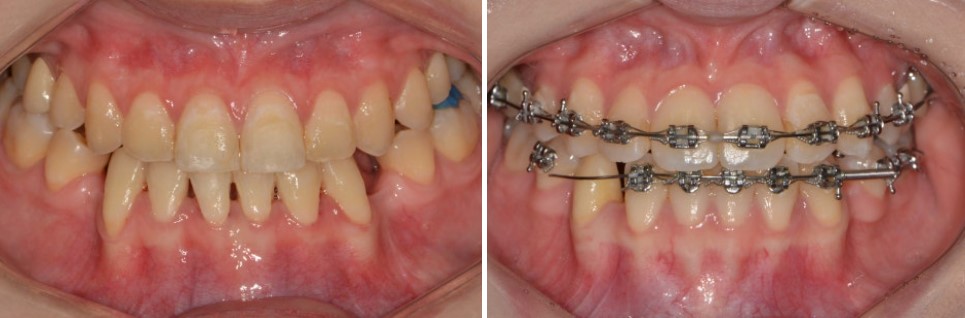

수술이 필요한데, 교정만 먼저 했다가 힘들어졌던 실제 사례

감이 잘 안 오실 수 있어서 실제 사례를 하나 소개해 드리겠습니다.

20대 자매분이 저희 병원에 내원하셨습니다.

마치 쌍둥이처럼 골격 구조도, 치아 상태도 매우 비슷한 케이스였습니다.

두 분 모두 주걱턱으로 인한 앞니 거꾸로 물림(반대교합) 이 고민이었고

다른 병원에서 아래 작은 어금니 2개를 발치한 뒤, 3년간 교정치료를 받으셨습니다.

하지만 결국 치료를 마무리하지 못한 채 서울리인치과교정과의원을 찾으셨습니다.

겉으로 입안만 빠르게 보면

“반대교합은 아닌 것 같은데, 치료가 잘 되어 가는 것 아닌가?”

라고 느끼실 수도 있습니다.

하지만 정밀 검사를 해보니,

위 앞니는 과도하게 앞으로 뻐드러진 상태였고

아래 앞니는 뒤로 심하게 쓰러져 있는 상태였습니다.

치아를 뽑아 만든 공간도 크게 남아 있는 모습이었습니다.

이는

수술이 꼭 필요한 골격성 주걱턱인데도,양악수술 없이 교정치료만으로 해결하려다 생긴 전형적인 부작용

이라고 할 수 있습니다.

결국 두 분 모두

기존 교정치료의 한계를 인정하고,

양악수술을 동반한 교정치료로 치료 계획을 변경하게 되었습니다.

이 사례는

치아교정에서 가장 중요한 것은무엇보다도 **“처음 진단의 정확성”**이라는 사실을다시 한 번 절실히 느끼게 해 준 경우였습니다.